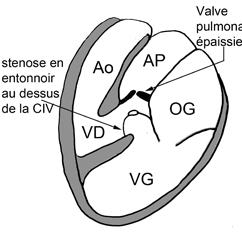

– Sténose pulmonaire : L’IRM aide à discriminer les atteintes valvulaires des obstacles sous ou sus valvulaires dans les cardiopathies congénitales.